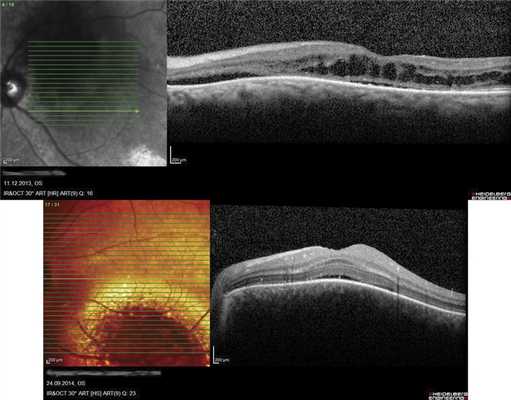

Методы обследования: визометрия, биомикроскопия, офтальмоскопия с помощью бесконтактной и контактной линз, оптическая когерентная томография, эхографическое исследование (В-скан), ангиография с флуоресцеином и индоцианином зеленым, микропериметрия с цветным фотографированием глазного дна. Для ТТТ при гемангиоме хориоидеи мы использовали диод-лазерные офтальмологические установки: Nidek-3300 (810 nm) и Iridex-IQ (577 nm). Суть метода лечения заключается в том, что диод-лазерная ТТТ осуществляется селективно только в фокусах неоваскуляризации, определяемых методом ФАГ или ангиографии с индоцианином зеленым, в ранней артериальной фазе, исключая структуры макулы и зрительного нерва (рис. 1). В связи с тем, что гемангиома хориоидеи - опухоль доброкачественная и нет необходимости лечения ее в пределах здоровых тканей, достаточно селективное лазерное воздействие на фокусы патологической неоваскуляризации хориоидеи, оберегая светочувствительные и светопроводящие структуры окружающих тканей. При остаточной опухоли после первого сеанса лечения проводятся повторные сеансы лазерного воздействия строго в зонах роста хориоидальных сосудов. Применяемые нами лазерное излучение длиной волны 810 и 577 нм, в отличие от 514-532 нм, проникает глубже и почти не поглощается структурами сетчатки на поверхности опухоли.

Результаты. При селективной лазерной ТТТ очагов неоваскуляризации, выявляемых в ранней артериальной фазе ангиографии, резорбция опухоли с прилеганием отслоенной сетчатки достигнута у всех 6 пациентов за 2-3 сеанса. Острота зрения улучшилась у 4-х и осталась без изменений - у 2-х пациентов (рис. 2). При микропериметрии световая чувствительность в центральной зоне сетчатки улучшилась у 2-х пациентов, сохранилась без перемен у 3-х и ухудшилась у 1-го пациента.

ОНЭ с отеком и дезорганизацией дисков наружных фоторецепторов в макулярной зоне выявлена у 12 больных с ГХ со снижением зрения до 0,02-0,8, проминенцией опухоли 1-4,05 мм и анамнезом заболевания от 1 мес до 15 лет. Наиболее выраженное снижение зрения (до сотых) отмечали в случаях пара- и макулярного расположения ГХ и длительности анамнеза более 10 лет (рис. 5, а), минимальное снижение остроты зрения (до 0,6-0,8) - при длительности анамнеза до 1 года (см. рис. 5, б).

Рис. 5. ОКТ-горизонтальный срез через макулярную зону. а - пациентки Е., Vis OS =0,02, длительность анамнеза 11 лет (ОНЭ, кистозные изменения в макулярной зоне с разрушением фоторецепторов); б - пациентки С., Vis OS =0,7-0,8, длительность анамнеза 6 мес (отечность наружных сегментов фоторецепторов).

В 8 случаях выявили распространенную зону ОНЭ с дезорганизацией фоторецепторного слоя «на протяжении» от очага (рис. 6, а). В 2 случаях при анамнезе более 15 лет были выявлены зоны разрушения слоя фоторецепторов и наружных слоев сетчатки, соответствующие зонам ранее существовавшей ОНЭ (см. рис. 6, б).

Рис. 6. ОКТ-горизонтальный срез «на протяжении» от ГХ. а - пациентки Х., длительность анамнеза 3,5 года (красными стрелками указана зона ОНЭ); б - пациентки К., длительность анамнеза 15 лет (желтыми стрелками указана зона разрушения слоя фоторецепторов и наружных слоев сетчатки на месте ранее существовавшей ОНЭ, атрофия РПЭ).